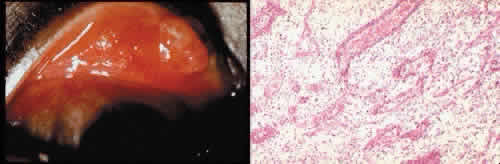

Granulation tissue often is the first type of reparative tissue in wound healing (Fig. 1). Although its composition varies somewhat, small-caliber vascular channels in a delicate collagenous stroma infiltrated by acute and chronic inflammatory cells generally characterize it. This amorphous tissue serves as a template for more definitive repair.

Fig. 1. Granulation tissue. A. Clinical photograph of granulation tissue (often mistakenly called a pyogenic granuloma) at the site of a ruptured chalazion. B. Granulation tissue growth in the region of a chalazion. The tissue has responded by forming multiple fine-caliber vascular channels associated with an infiltrate of acute and chronic inflammatory cells. The lightly stained areas in the tissue represent the response of fibroblasts and vascular endothelial cells to alter and augment the extracellular matrix. (Hematoxylin-eosin stain; × 100.)